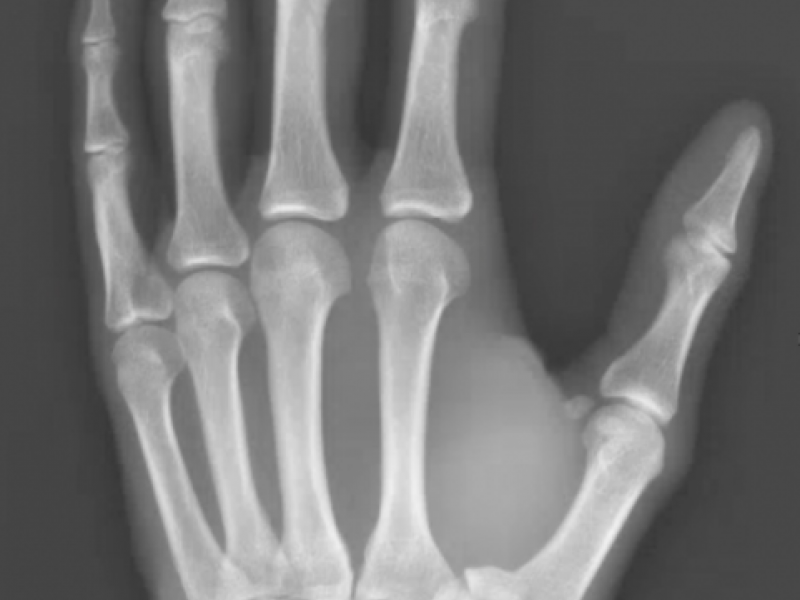

What's the Diagnosis? By Dr. Chris Smith

A 31 yo male presents with left thumb pain after a dirt bike